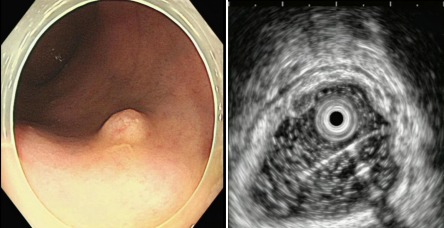

【医声守护·科普】第53期:粘膜下隆起性病变是什么?需要手术吗?